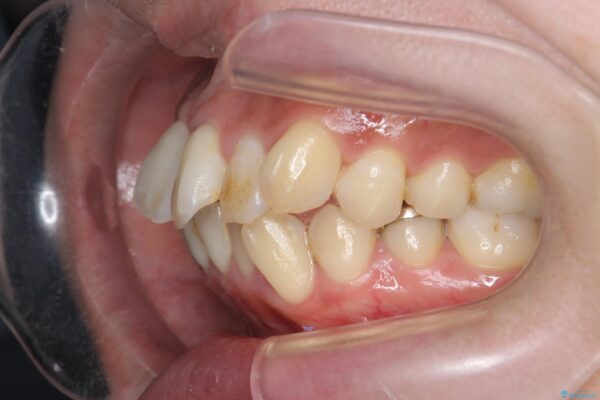

治療を終えて

患者様の協力度も高く、リファインメントなしで治療を終えることができました。

抜歯をしない場合、多くは歯と歯の間を少し削ることでスペースを作ります。

動的治療期間は約4か月となり、短い治療期間で前歯のガタつきが改善され大変喜んでいただけました。

治療後

気になる犬歯のガタつきをマウスピース矯正で改善 治療後画像 気になる犬歯のガタつきをマウスピース矯正で改善 治療後画像 気になる犬歯のガタつきをマウスピース矯正で改善 治療後画像 気になる犬歯のガタつきをマウスピース矯正で改善 治療後画像